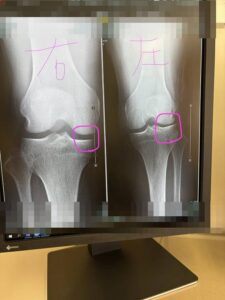

重度の外反母趾の方の症例です。

歩くときの傾きを計測しました。